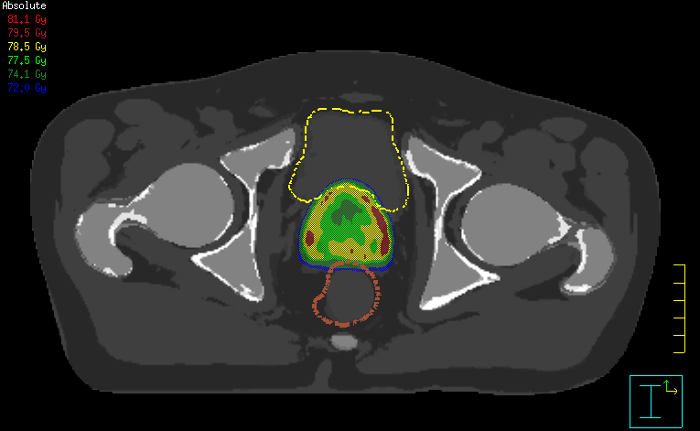

With its exceptional soft-tissue visualization capabilities and wide range of image contrasts, MRI has become a powerful tool to help more precisely define tumor boundaries. This is particularly important as it has been established that there is a high degree of uncertainty in target volume delineation, and it is even reported to represent the largest uncertainty in the entire radiotherapy process for most tumor sites**. Better visualization of the target area and nearby organs-at-risk is a key factor in enhancing target volume delineation. MRI’s expanding role also can be attributed to its functional imaging capabilities, which can inform both target characterization and treatment response.

With its superior soft tissue contrast compared to CT, MRI offers exquisite visualization of tumor boundaries and proximity to nearby critical structures.

The ability to tune contrasts can provide even more valuable information about tumor characteristics and tumor extent to facilitate enhanced delineation, and also provides possibilities for dose boosting strategies.

Innovative strategies in MRI-only simulation have made it possible to derive CT-like electron density information from MR imaging data. This capability enables physicians to use MRI as the radiotherapy department’s primary imaging modality for specific applications to eliminate tedious and error-prone CT-MR registration and simplify workflows.